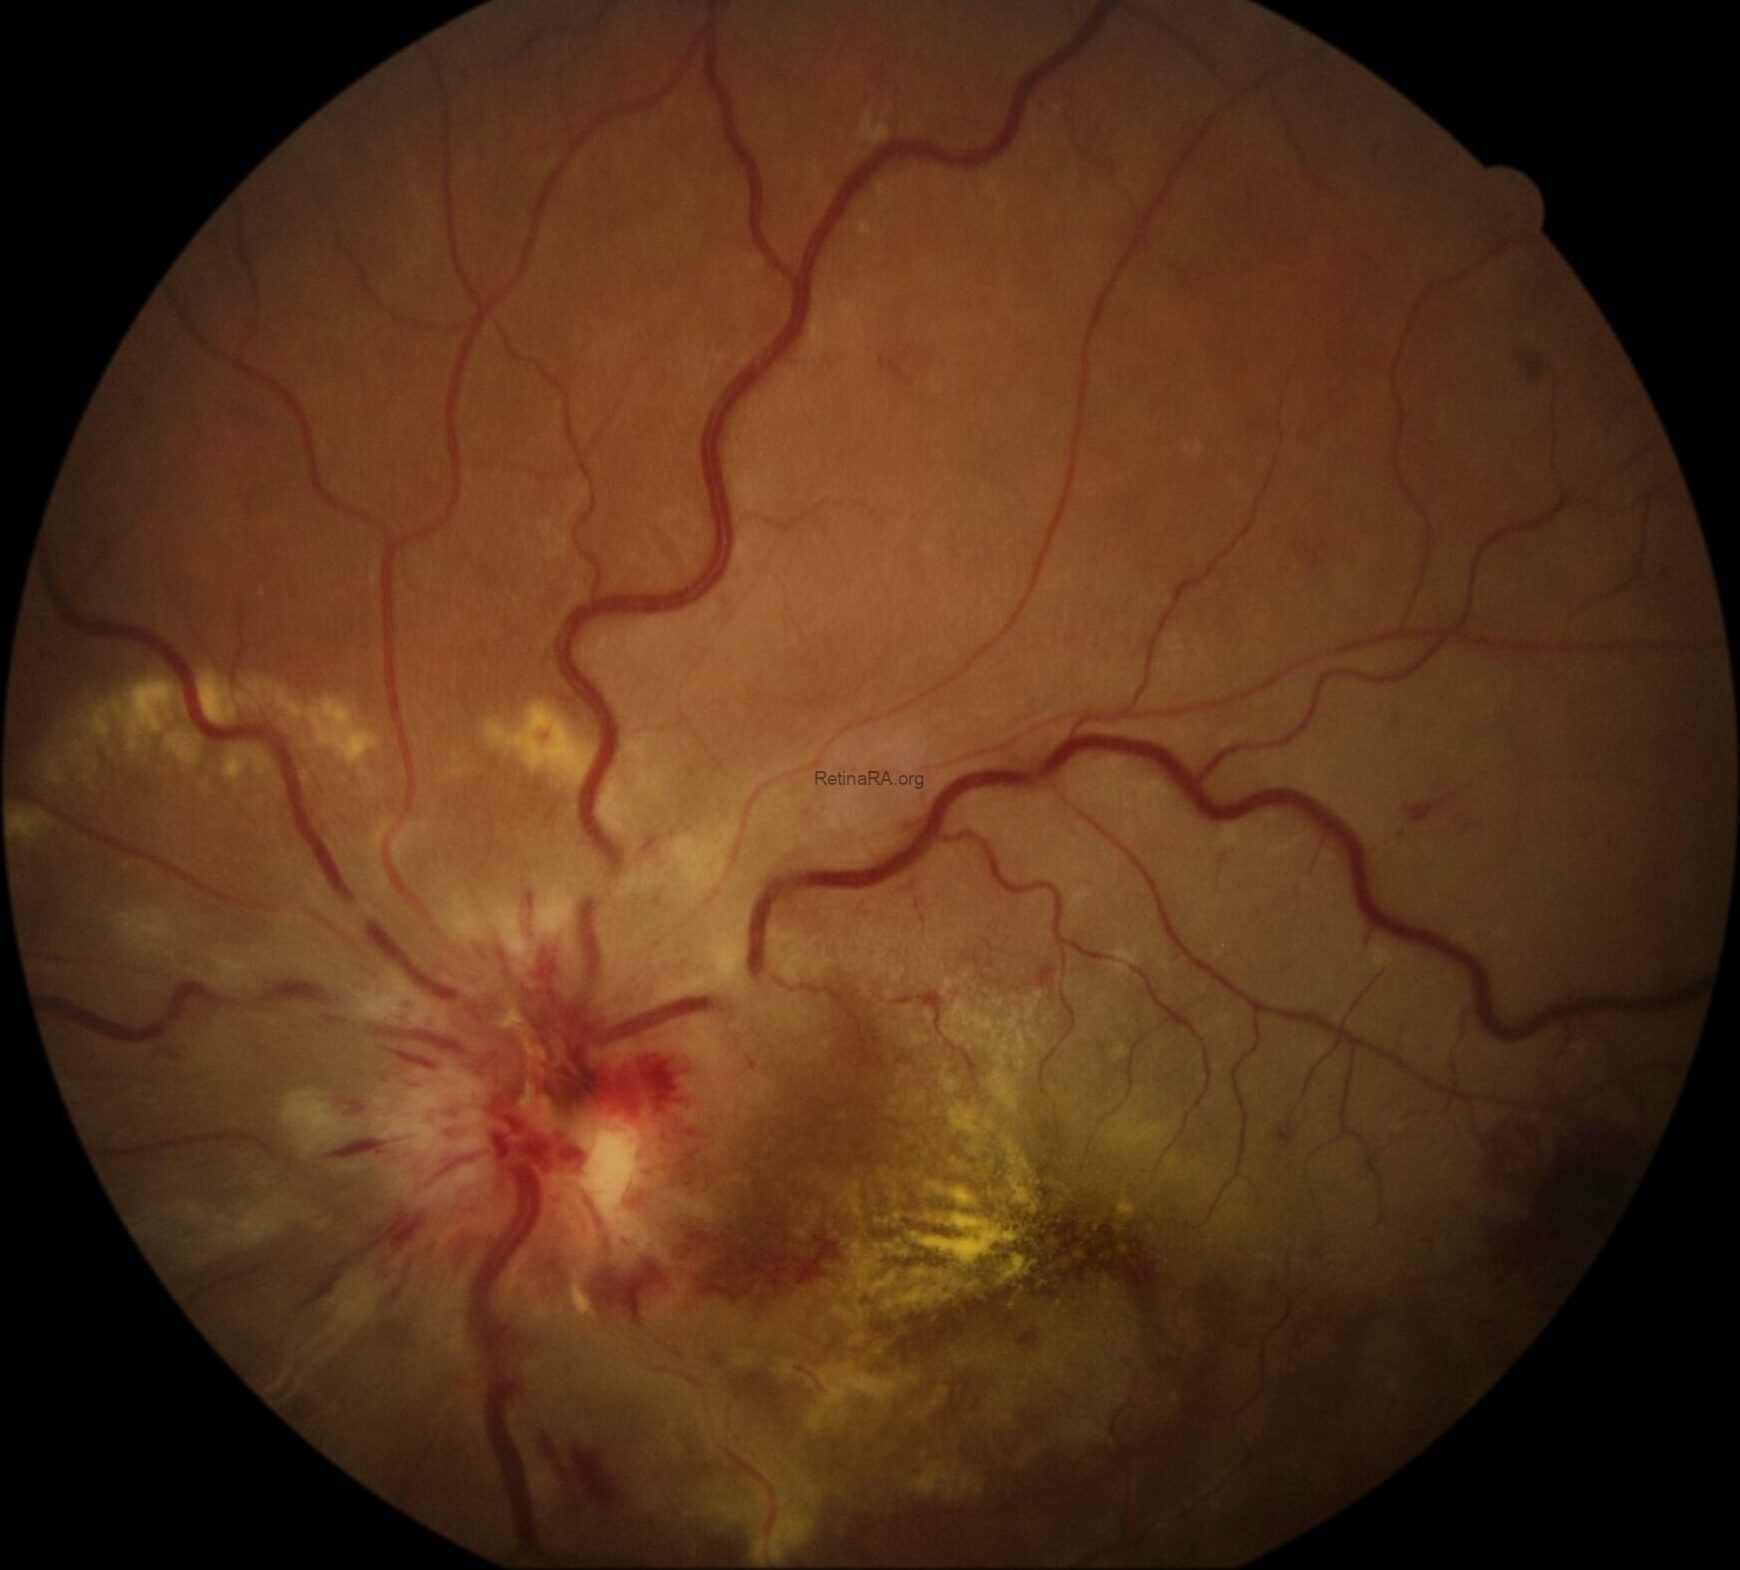

A patient presented with a complaint of sudden loss of vision in the right eye. Fundoscopic examination revealed mild venous dilatation and tortuosity, optic disc edema, flame-shaped retinal hemorrhages around the disc, cotton-wool spots (soft exudates) in the nasal quadrant, and lipid exudates (hard exudates) forming a macular star pattern around the fovea. Additionally, the superior temporal quadrant of the retina was noticeably pale, and there was mild paleness around the inferior temporal branches of the retinal vein (white arrows).

Based on the clinical findings, the patient was diagnosed with SLE-associated neuroretinitis (stellar) and BRAO. The pallor around the inferior temporal vein branches was interpreted as perivenular fern-like PAMM (white arrows). Furthermore, the presence of venous dilatation, vascular tortuosity, and perivenular fern-like PAMM suggested that, although the patient did not have complete CRVO, there may have been a partial occlusion of the central retinal vein due to optic nerve head stasis.

It was concluded that the coexistence of neuroretinitis, BRAO, and PAMM was secondary to SLE-associated thrombotic tendency and vasculitis. Compared with diabetic retinopathy and hypertensive retinopathy, the more occlusive nature of SLE retinopathy generally leads to more profound ischemia.